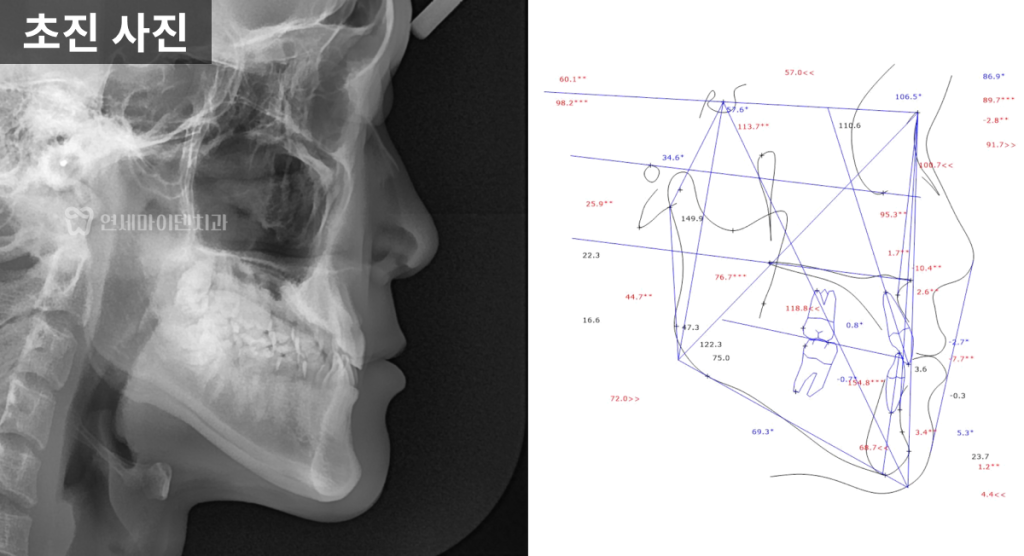

3급 부정교합 진단

방사선 사진 분석 결과,

위턱보다 아래턱이 더 발달한

3급 부정교합,

흔히 주걱턱이라고 불리는 상태였습니다.

아래 앞니의 각도는

정상치보다 훨씬 작은 68.7도로,

안쪽으로 심하게 쓰러져 있었습니다.

정면 방사선에서는

위턱과 아래턱의 폭 차이가 크게 나타났으며,

위턱이 약 10mm 이상 좁은 상태임을

확인할 수 있었습니다.